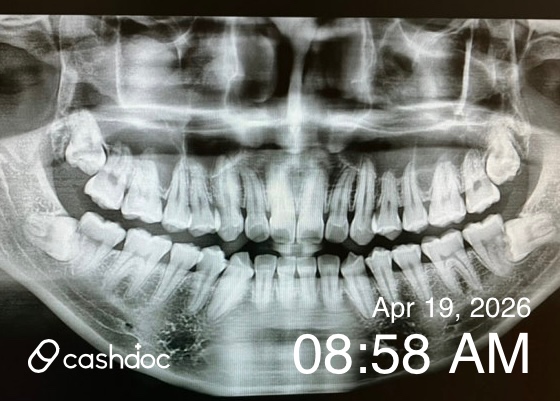

v 처음 가게 된 계기 : 가족들이 기존에 다니던 치과가 있었는데 아빠의 임플란트 치료를 위해 다른 치과 3군데를 상담하며 알아보다가 친절하고 꼼꼼한 상담, 진료로 만족해서 성심49플란트 치과의원으로 옮기게 되었어요. 성심49플란트 치과의원은 의사선생님들이 통합치의학과 전문의 2명, 치과보존과 1명 총 3분의 의사선생님이 임플란트, 교정과, 보철과, 충치 등 분야별로 나뉘어서 진료해주신다고 하기에 더 전문적인 느낌이여서 가게 되었어요. v 방문 전 걱정했던 점이나 망설였던 이유 : 나이가 들어가면서 치아도 노화를 느끼는 것 같아요. 잇몸이 약해진 것 같은 느낌과 치아 건강검진을 위해 방문하였는데 혹시나 충치나 신경치료 등 치아의 상태가 좋지 않아 치료를 해야 하는 상황이 될까 걱정이 되더라고요. v 실제 병원 분위기, 상담 과정, 설명은 어땠는지 : 성심49플란트 치과의원은 최신형 엑스레이 촬영을 하고 치아의 전반적인 상태를 꼼꼼히 모니터하고 치아상태에 대해서 이야기를 해주어요. 진료, 치료를 해주시는 의사쌤들도 분야별로 전문의들이고 친절하셔서 만족스러워요. 병원 의료진분들도 많고 상담도 상담간호사가 따로 해주고 꼼꼼히 안내해주고 상담해주어서 신뢰가 가는 곳이예요. (시술 전 찍어논 사진이 없어서..느낌만 보세요) (치아 노출 때운 후 제 사진) v 시술을 받았다면, 결정하게 된 이유 : 치과 정기검진으로 치과를 방문하게 되었고 스케일링을 받고 치아 아랫니 부분의 잇몸이 살짝 내려가서 아랫니 치아 1개가 뿌리부분이 살짝 노출이 되는 부분이 있었어요. 이렇게 되는 경우 지금 상태는 괜찮더라도 미관상에도 예쁘지 않기도 하지만 잇몸이 내려가면 치아의 신경이 자꾸 자극을 받게 되어 음식물을 섭취했을 때 치아가 시리거나 통증이 있을 수 있다고 했어요. 치아 때우기 시술은 시간도 오래 걸리지 않고 가격부담도 크지 않아서 치아 아랫니 부분을 레진으로 때우는 시술을 하기로 하였어요. v “처음이라서” 느꼈던 솔직한 감정들 : 치아치료는 충치, 신경치료, 임플란트만 생각했었는데 노화에 따라 잇몸도 내려가는 부분도 있어서 나이가 들수록 더 신경써야겠다는 생각이 들더라고요. 치아가 노출된 부분은 생각보다 빠르고, 티가 나지 않게 레진으로 때우기 때문에 간단한 시술이라고 생각했어요. 치아가 노출되지 않으니 더 깔끔해보이더라고요. v 다음에 다시 방문할 의사가 생겼는지 : 성심49플란트 치과의원은 치과 분야별로 세부화된 전문의들이 계시고 간호사, 병원 스텝분들도 많고 의사, 스텝분들이 다 친절하셔서 다시 방문하게 되더라고요. 그래서 온가족이 성심49플란트 치과의원로 옮겨 치과정기 검진과 다른 치과에 관한 치료도 성심49플란트 치과의원에 다니게 되었어요.

서울 믿음치과에서 오래된 보철 치료받은 후기 공유합니다. 10년전에 오른쪽 상악 어금니 골드 크라운 치료했었는데요. 오래되다 보니.. 미세하게 실금이 가서 치과 내원했어요. 치과는 늘 공포의 병원인데.. 서울 믿음치과는 원장님과 치위생사분이 다 친절하셔서 마음이 놓이더라구요. 파노라마 사진찍고 치아 전체 점검받았구요. 다른 치아는 이상이 없고. 금니에 금이 가서 교체했습니다. 지르코니아 크라운으로 교체했고.. 원장님이 꼼꼼하게 잘 치료해주섰어요. 앞으로 서울 믿음치과에서 치아 점검 받으려고 합니다. 무엇보다 과잉진료 없어서 정말 믿음이 가는 치과입니다.